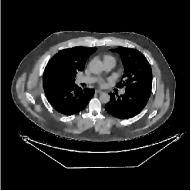

This section compares the reconstruction quality and runtime among the proposed MBIR method, PWLS-ST-, and other three MBIR methods, PWLS-EP, PWLS-DL, and PWLS-ST-. Table I shows that, for both 2D and 3D sparse-view CT reconstructions of the XCAT phantom, the proposed PWLS-ST- model outperforms PWLS-EP and PWLS-ST- in terms of RMSE. In addition, PWLS-ST- using a square transform (of size ) achieves lower RMSE than PWLS-DL using an overcomplete dictionary (of size ) for 2D sparse-view reconstructions. Fig. 3(a) and Fig. 4 show the reconstructed images for 2D and 3D phantom experiments, with different reconstruction models and different number of views. (See the corresponding error maps in the supplement.) The proposed PWLS-ST- consistently gives more accurate image reconstructions compared to other MBIR methods. Specifically, PWLS-ST- has smaller errors in the heart region (see zoom-ins in Fig. 3(a)) of 2D reconstructions than PWLS-DL and PWLS-ST-. In addition, compared to PWLS-ST-, PWLS-DL and PWLS-ST- have some ringing artifacts around the edges with high transition, e.g., edges between air and soft tissues. (See a comparison of profiles of PWLS-ST- and PWLS-ST- in the supplement.) In particular, PWLS-ST- and PWLS-DL give more visible ringing artifacts for 2D reconstruction from fewer views, and PWLS-ST- has these ringing artifacts for 3D reconstructions regardless of the number of views (see zoom-ins in Fig. 4). Table II reports runtimes of different MBIR methods in reconstructing the -views XCAT phantom scan. (FBPConvNet is a non-MBIR method and its runtime for processing a image is approximately one second with a TITAN Xp GPU.) While providing better reconstruction quality, the proposed Algorithm 1 of PWLS-ST- has shorter runtime compared to the algorithms of PWLS-DL and PWLS-ST- in Section III-A. Similar to the PWLS-EP algorithm, the reconstruction time of the PWLS-DL, PWLS-ST-, and PWLS-ST- algorithms can be further reduced by using ordered subsets [51].

Fig. 3(b) shows that when tested on the clinical scan data, the proposed PWLS-ST- method improves reconstruction quality in terms of noise and artifacts removal (e.g., see zoom-ins for soft-issue regions), and edge preservation (e.g., see zoom-ins for bone regions), compared to PWLS-EP and PWLS-ST-. Compared to PWLS-DL, PWLS-ST- achieves comparable image quality, but requires less computational complexity.

The benefit of the proposed PWLS-ST- over PWLS-ST- can be explained when there exist some outliers for some : in (12) gives equal emphasis to all sparse codes – from small to large coefficients that generally correspond to edges in low- and high-contrast regions, respectively – in estimating ; however, PWLS-ST- adjusts to mainly minimize the outliers, i.e., it may not pay enough attention to reconstruct regions with small coefficients. The histogram results in Fig. 1 reveal model mismatch of PWLS-ST- over the iterations. Fig. 3, Fig. 4, and Table I show that PWLS-ST- can moderate model mismatch, and provides more accurate reconstruction than PWLS-ST-.

| (a) 2D fan-beam CT experiments |